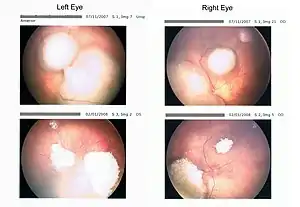

| Rb tumors taken with a retinoscan before and during chemotherapy | |

- Systemic chemotherapy has become forefront of treatment in the past decade, in the search for globe-preserving measures and to avoid the adverse effects of EBR therapy. The common indications for chemotherapy for intraocular retinoblastoma include tumors that are large and that cannot be treated with local therapies alone in children with bilateral tumors. It is also used in patients with unilateral disease when the tumors are small, but cannot be controlled with local therapies alone.

- Chemoreduction is a combined approach using chemotherapy to initially reduce the size of the tumor, and adjuvant focal treatments, such as transpupillary thermotherapy, to control the tumor.[35][36]